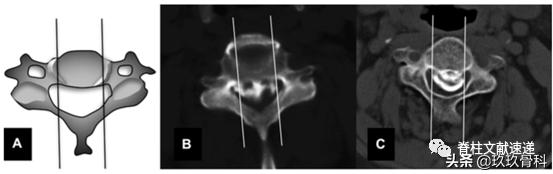

下图所示为骨化块宽度评估,图B为宽基底骨化块,易残留。

术前应仔细阅片,明确骨化块与椎弓根的关系,B、E易切开,D、G易残留。